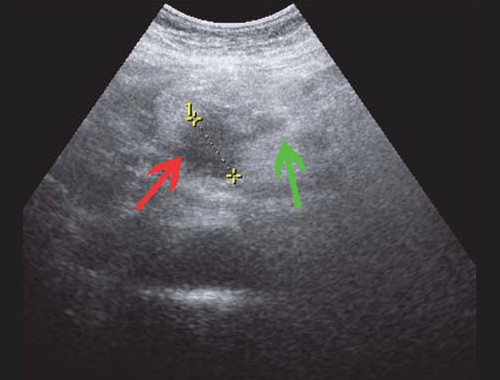

Рис. 4. Ультразвуковая картина опухоли головки ПЖ: образование в головке ПЖ (красная стрелка), расширенный панкреатический проток (зеленая стрелка).